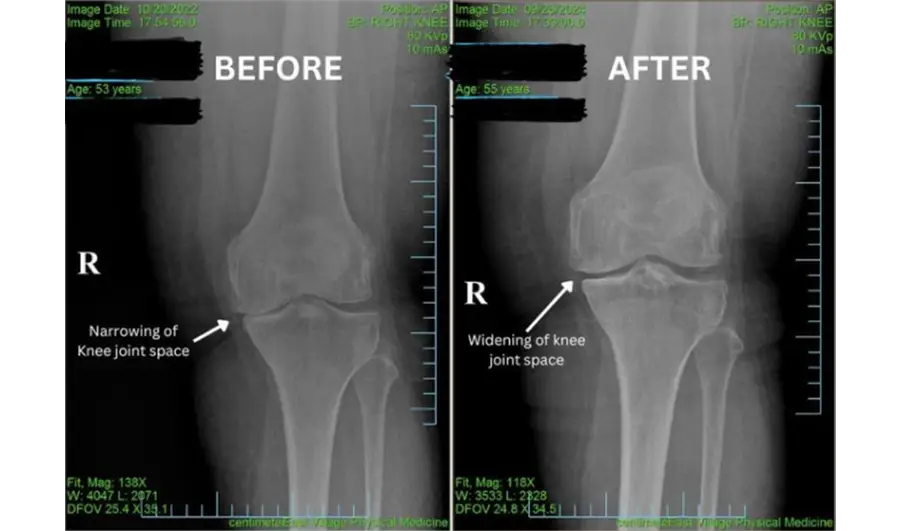

We are seeing spectacular results with our unique knee protocols:

• Relief with Knee Decompression: Gently relieves joint pressure, restores space, and reduces inflammation to improve movement.